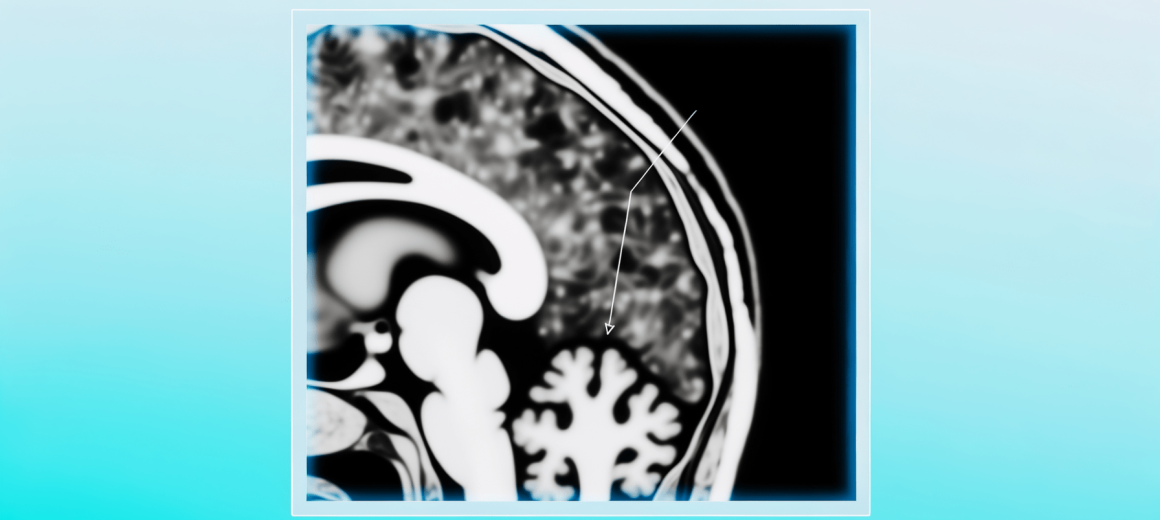

Le patologie neurologiche rappresentano un altro campo di applicazione delle CNN. Le tecnologie a risonanza magnetica funzionale (fMRI) e tomografia computerizzata (CT) consentono di ottenere dettagliate immagini cerebrali. Un’applicazione chiave delle CNN è la diagnosi precoce del morbo di Alzheimer e di altre condizioni neurodegenerative. Gli algoritmi di deep learning analizzano le immagini cerebrali, identificando i cambiamenti nelle strutture neurali che possono indicare l’insorgenza di patologie. Alcuni algoritmi sono in grado di rilevare segni di deterioramento cognitivo anni prima che i sintomi si manifestino clinicamente, permettendo interventi precoci che possono rallentare la progressione della malattia.

Un esempio notevole di questa collaborazione tra uomo e macchina è l’uso delle CNN nella chirurgia guidata da immagini. Durante interventi complessi, come quelli neurochirurgici, le CNN possono analizzare costantemente le immagini ottenute da scanner intraoperatori, fornendo feedback istantaneo ai chirurghi su eventuali anomalie o deviazioni dal piano chirurgico previsto. Questo tipo di supporto non solo aumenta la sicurezza dei pazienti, ma migliora anche le probabilità di successo delle operazioni complesse.